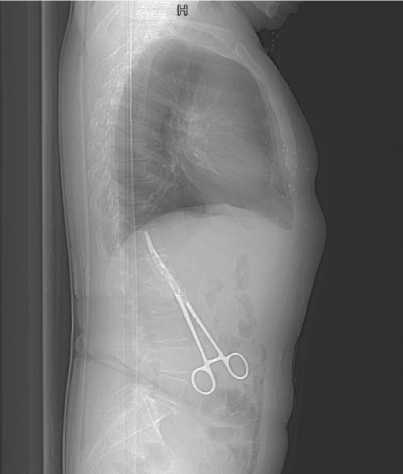

В 2019 г. обратилась к врачу по месту жительства с болями в поясничном отделе позвоночника, при рутинном R-исследовании был обнаружен металлический инородный предмет в правой половине брюшной полости – хирургический зажим. Несмотря на разъяснения хирургов о возможных рисках и осложнениях, пациентка отказалась от предложенного планового оперативного удаления инородного тела, сославшись на отсутствие беспокоящих симптомов.

На последующем КТ-исследовании брюшной полости чётко визуализировано инородное тело подпечёночного пространства со сформированным абсцессом брюшной полости (рис. 4, 5).

Рисунок 4. КТ-визуализация инородного тела (хирургического зажима) брюшной полости

Figure 4. CT imaging of a foreign bode (surgical clamp) in the abdominal cavity

Рисунок 5. КТ-визуализация инородного тела (хирургического зажима) брюшной полости

Figure 5. CT imaging of a foreign bode (surgical clamp) in the abdominal cavity